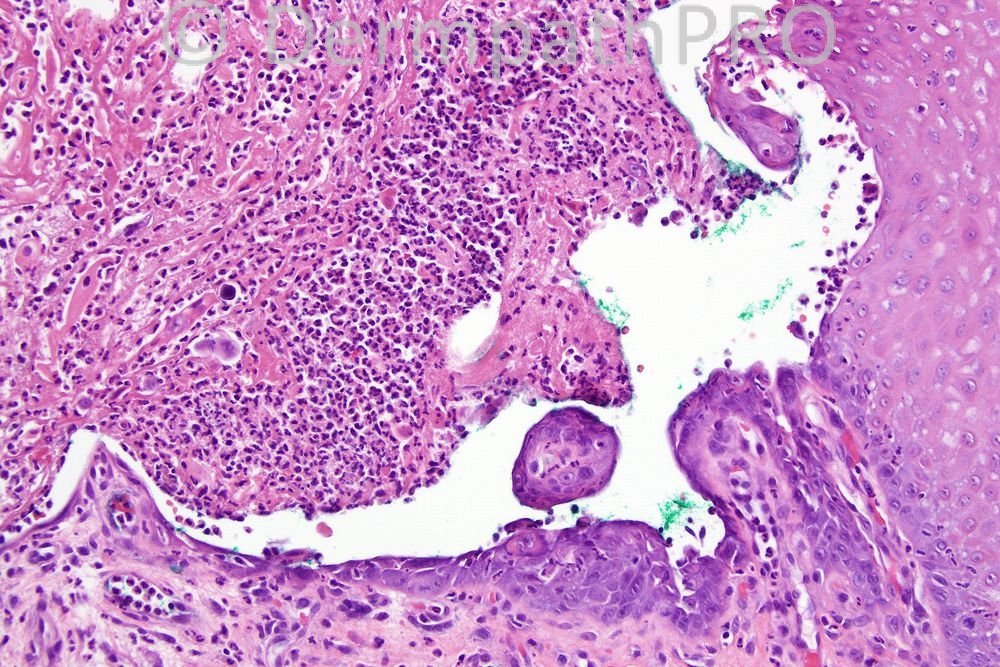

Female 76 years, ulcerated lesion in mouth.